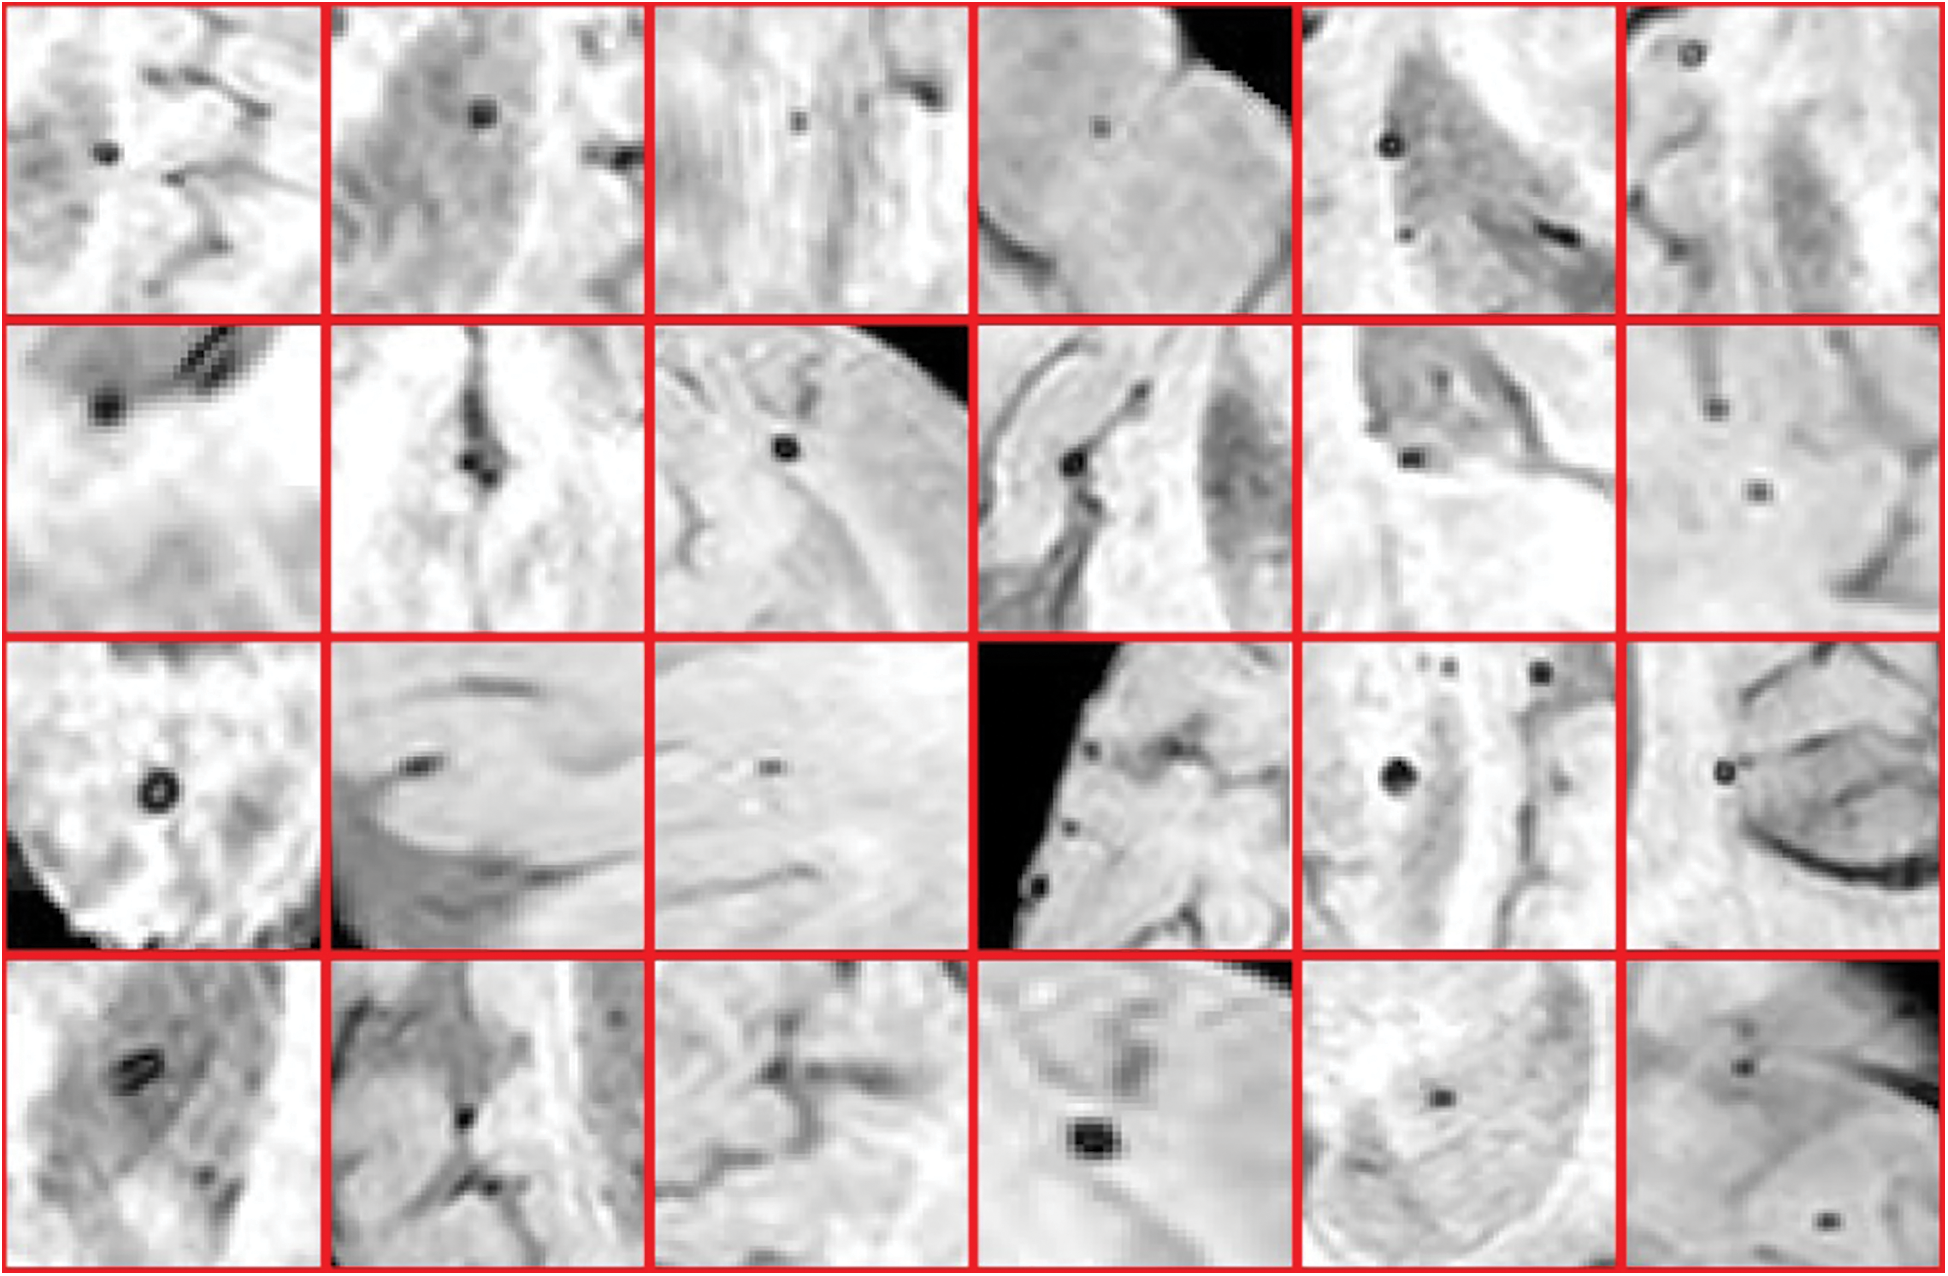

Furthermore, in detecting CMBs by utilizing a regular k-mean approach the desired results are difficult to achieve. We made changes in the traditional approach as it is not powerful enough for CMBs. We are required to design a more efficient algorithm that can handle this difficult problem without depending upon pre-processing and other steps. To get smooth and accurate detection if any non-micro bleed part is detected as CMBs, it will highly impact the overall classification of neuroimaging. Figs. 9 and 10 show the Non-CMBs and CMBs region in brain images, respectively.

Figure 9: 6 × 4 = 24 samples of false classes of Non-CMBs particles

Figure 10: 4 × 6 = 24 samples of true classes having CMBs in brain MRI